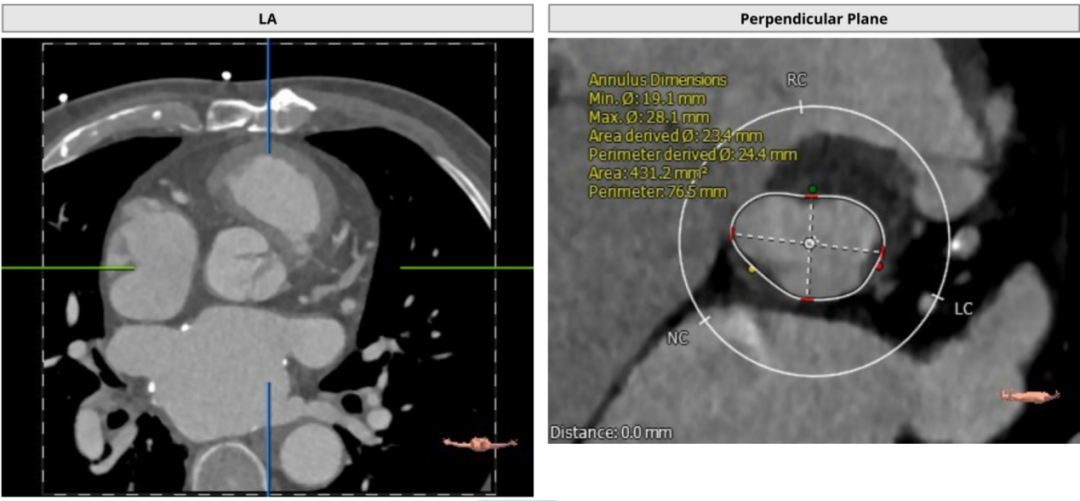

术中DSA影像:

造影检查瓣周漏

TAVR术后造影无瓣周漏